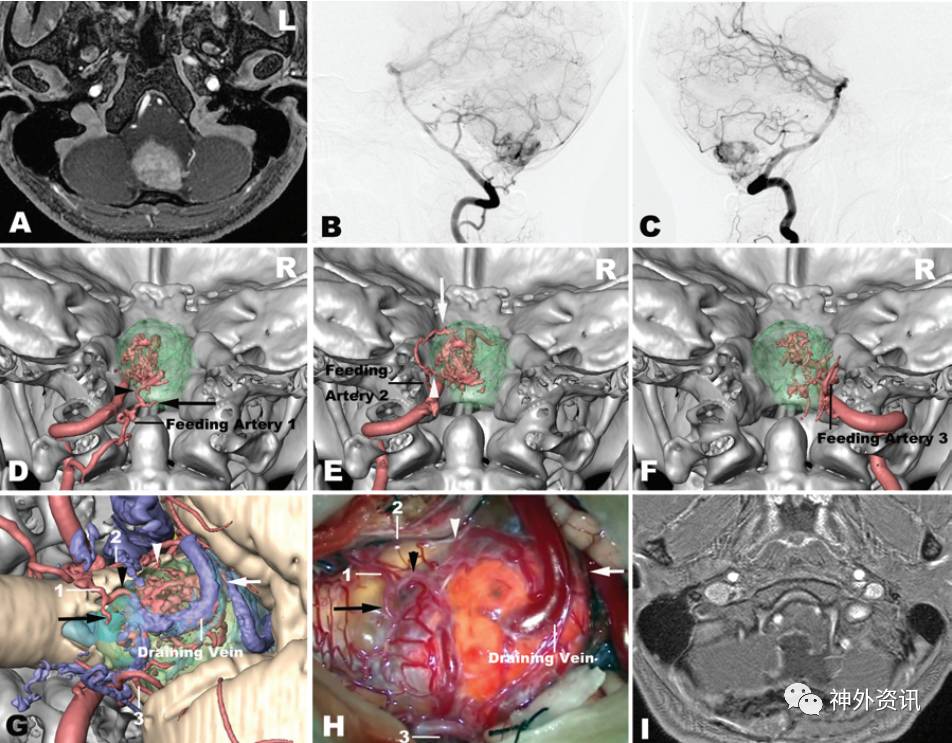

图1. 病例2的影像学资料和hr-3DMMI图像。A.MRI水平位T1加权增强成像显示位于延髓背侧的血管母细胞瘤;B.DSA左侧椎动脉造影侧位片;C.DSA右侧椎动脉造影侧位片;D-F.hr-3DMMI显示肿瘤供血动脉;G.hr-3DMMI显示肿瘤供血动脉与周围结构毗邻关系;H.术中所见肿瘤供血动脉分布与术前hr-3DMMI一致;I.术后MRI水平位T1加权增强成像显示肿瘤全切除。